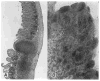

Abdominal multivisceral allotransplantation (MVTX) from Brown Norway donor rats to Lewis recipient rats was performed under a 14-day course of low (0.32 mg/kg) or high-dose (0.64 mg/kg) intramuscular FK 506 to which weekly further injections were added in some of the high-dose animals. With all three regimens, long survival was frequently achieved with good intestinal adsorption and weight gain, but histopathologic evidence of intestinal rejection existed in the most lightly treated animals. The liver, stomach, and pancreas had only minor abnormalities. Rejection of isolated intestinal grafts was more difficult to control based on histopathologic criteria, and satisfactory results were obtained only with the most aggressive treatment protocol, suggesting that the liver in the MVTX had provided an advantage to the companion organs of the graft, of which the intestine was most vulnerable. Histopathologically, the lymphoid elements of the intestine, including the Peyer's patches, appeared to be the most immunogenic component of the intestine. Epithelium near lymphoid areas was secondarily involved with villous atrophy, cryptitis, and abscess formation. Beginning within 12 days in successful MVTX experiments, the lymphoreticular components of the graft intestine, including the Peyer's patches, lamina propria, and mesenteric nodes, were shown with anti-Ia monoclonal antibodies to be repopulated with recipient cells. This finding in grafts that appeared to be permanently accepted was surprising and contrary to expectations from the literature on intestinal allotransplantation.